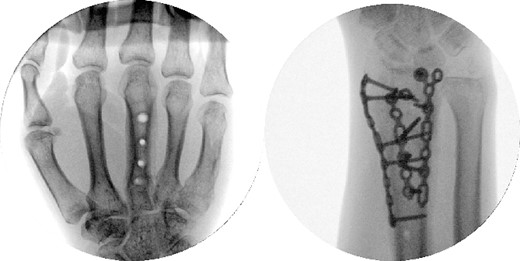

A dorsal spanning plate was planned to treat the fracture. An incision was made over the third dorsal compartment followed by release of the fourth dorsal compartment to fully visualize the fracture. Once the plate was placed, intraoperative fluoroscopy revealed that that radial styloid was still displaced. After releasing the first dorsal compartment and brachioradialis, a radiostyloid plate was then placed. Additionally, the volar ulnar corner of the radius was still not reduced properly, so a Protean fragment specific volar buttress plate was placed. Final intraoperative fluoroscopy films revealed satisfactory reduction and alignment (Figs 3 and 4).

Two weeks following the procedure, the patient returned to the clinic for a follow-up visit. The wrist was swollen and ROM was limited. Hand motor functions and neurovascular exam were fully intact. Radiographs taken in clinic showed intact hardware with healing fracture. At 2 months follow-up, radiographs showed intact hardware with interval bone bridging across fracture sites. Radiographic parameters including articular alignment, radial height, radial inclination, and volar tilt were in acceptable ranges (Fig. 5). The patient reported no concerns or complications. A computed tomography (CT) scan was obtained at 10 weeks after the procedure and confirmed adequate bony healing and alignment without failure (Fig. 6). The dorsal spanning plate was eventually removed 1 month later and 4 months since the initial operation (Fig. 7).

Radiological assessment at 2 months postprocedure with PA and lateral views.